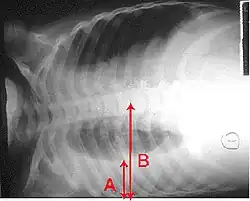

-

Pneumonia seen by ultrasound[78]

Pneumonia seen by ultrasound[78] -

Right middle lobe pneumonia in a child as seen on plain X-ray